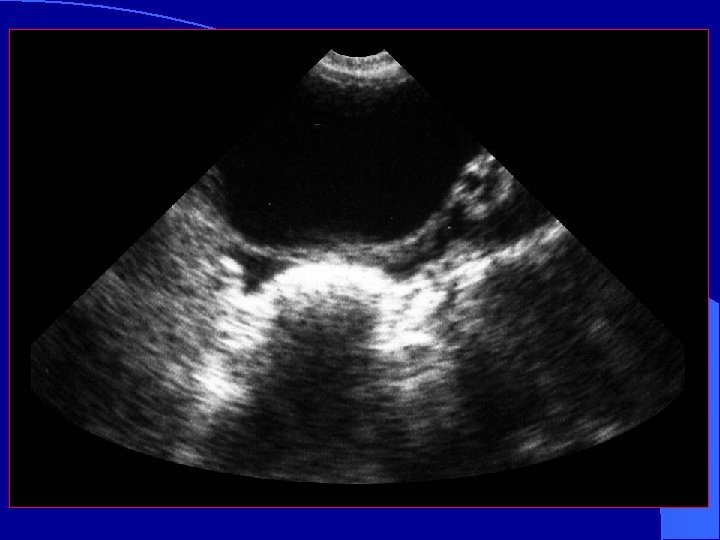

To Evaluate the Thorax l Move probe – cephalad – longitudinal l Image Liver Diaphragm Pleural space

Hemothorax liver fluid diaphragm

Small Pleural Effusion Large Pleural Effusion

Ma O John, Mateer J, Trauma Ultrasound Examination Versus Chest Radiography in the Detection of Hemothorax Ann Emerg Med: March 1997 l 240 trauma US study patients l 26 had hemothorax ( CT or chest tube) l CXR and US – 0 false positive – 1 false negative – 25 true positive – 214 true negative